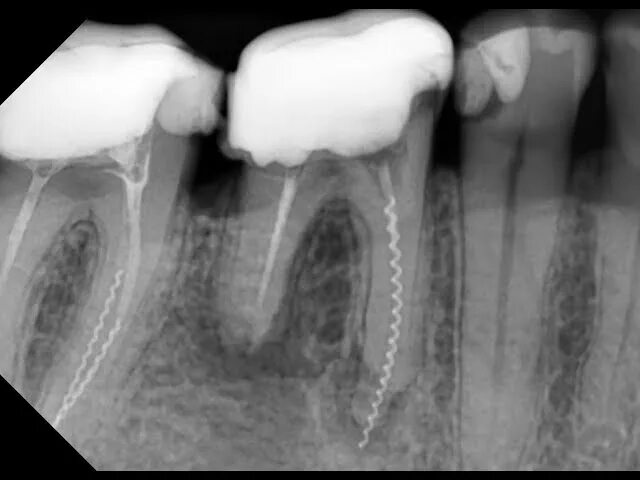

Пломбирование перфорации